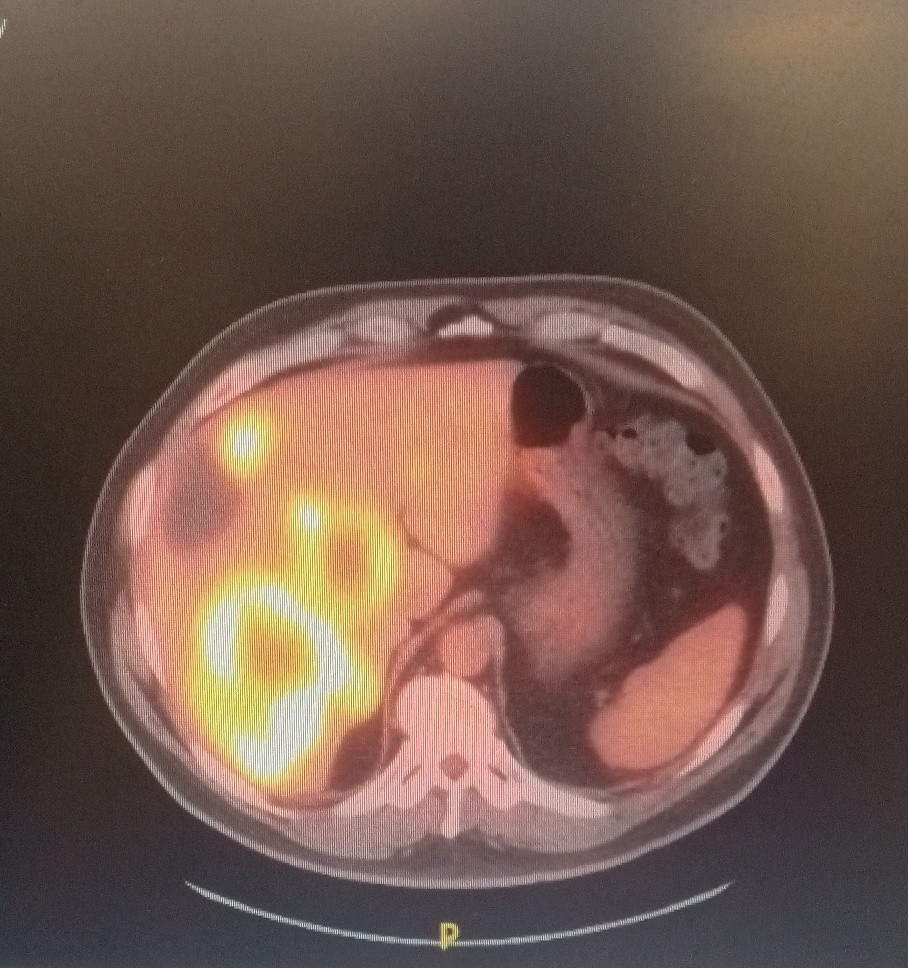

The patient is a 59-year-old male who was accidentally found to have liver lesions when he underwent (CTA) computed tomography angiography for chest pain (Figure 1). A subsequent positron emission tomography scan (PET) revealed metastatic disease in the liver (Figure 2), most likely originating from the primary sigmoid colon cancer (Figure 3). CT-guided liver biopsy of the liver lesion confirmed metastatic disease with histologic features consistent with a primary of colorectal origin. His blood test showed elevated colonic embryogenic antigen (CEA) of 38 ng/ml.

Figure 2. PET scan showing multiple Liver metastasis

Figure 2